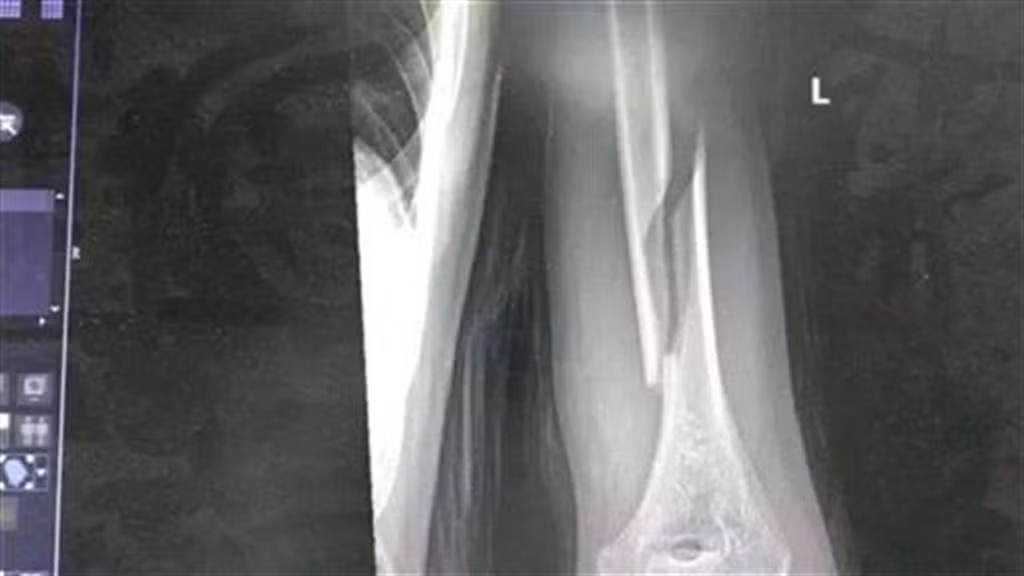

Ngay sau đó, anh đã đưa con trai đến bệnh viện để cấp cứu. Tại bệnh viện, sau khi chụp X-quang, các bác sĩ cho biết, trường hợp gãy tay của con trai anh rất nghiêm trọng.

Theo các bác sĩ, xương cánh tay là bộ phận cứng rắn nhất trên cơ thể con người. Thế nhưng lại bị vặn gãy, hơn nữa gãy kiểu xoắn ốc, uốn lượn rất kỳ quái, rất khó điều trị, phải lập tức phẫu thuật.